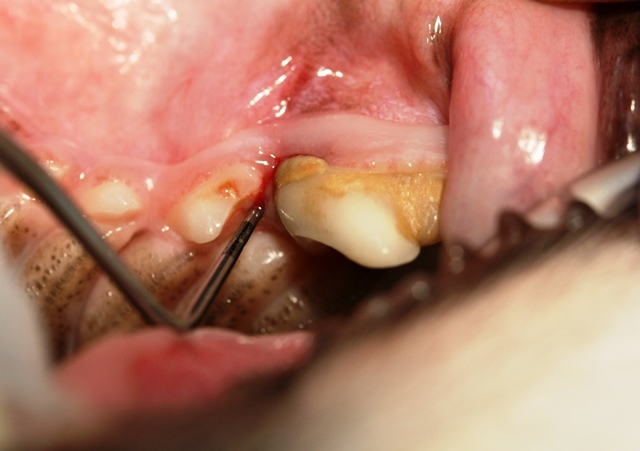

Der Chihuahua-Rüde ist sozusagen unser Zahnvorzeigepatient, und wir freuen uns jedes Jahr über seine topgepflegten Zähne, doch leider kam es anders als erwartet. Im Rahmen der gründlichen Untersuchung, die zu jeder Impfung dazugehören sollte, durfte uns Pico seine Zähne zeigen. Schnell fielen Rötung, Schwellung und Rückbildung des Zahnfleisches  im Bereich der vorderen Wurzel des Reißzahnes im linken Oberkiefer auf (Bild 1). Außerdem wies dieser Zahn im Vergleich zur Gegenseite eine deutliche Zahnsteinbildung auf. Die Parodontalsonde, ein spezielles Instrument mit einer Skalierung zum Ausmessen von Zahnfleischtaschen, brachte das Ausmaß des Schadens an das Licht. Die Sonde ließ sich fast einen Zentimeter tief in das Zahnfach einführen (Bild 2+3).

Was war geschehen? Trotz Zahnpflege hatte sich zwischen Zahnfleisch und Zahn eine Tasche gebildet, in die Bakterien eingedrungen waren. Die nachfolgende Entzündung hatte den Zahnhalteapparat erfasst und war jetzt bereits tief in das Zahnfach eingedrungen. Es war bereits zum Knochenabbau und zur Lockerung gekommen. Der Zahn war nicht mehr zu erhalten und musste leider entfernt werden.